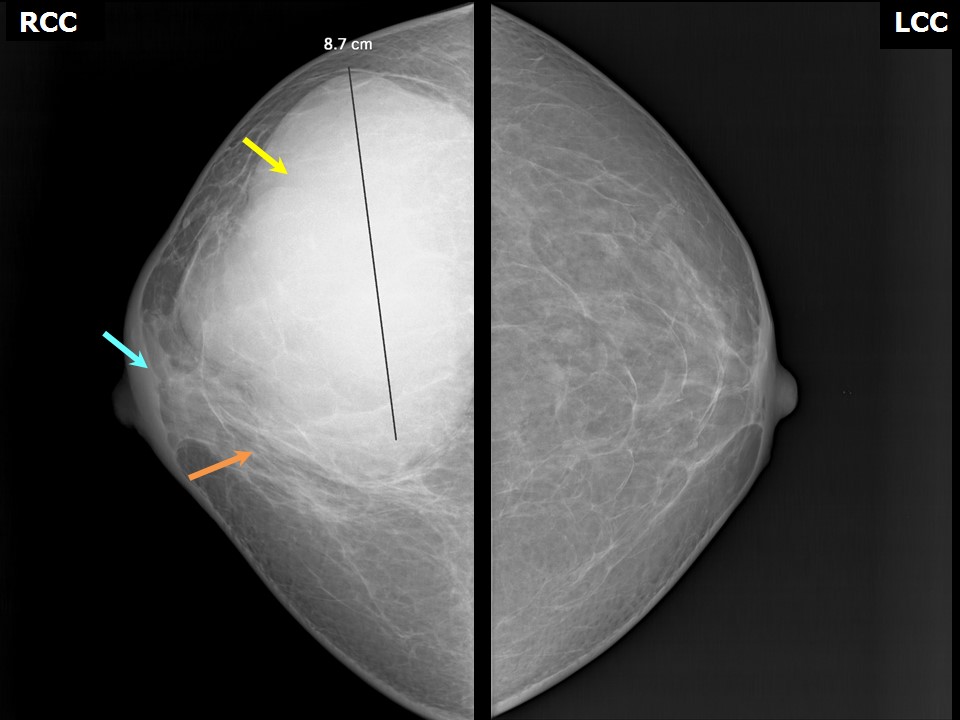

Что такое маммография: важность, процесс и результаты

Раздел: Необычные решения